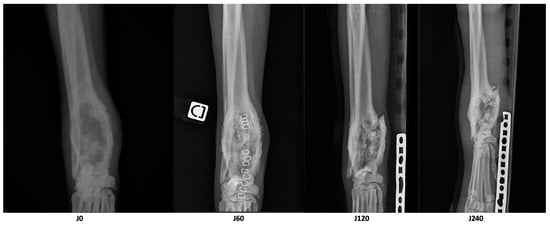

3. Results

| Parameter | D0 | D60 | D210 | Variation D60/D0 | Variation D210/D0 |

|---|---|---|---|---|---|

| Longest diameter of the osteolytic area (cm) | 8.1 | 6.7 | 6.1 | −17% | −25% |

| Volume of dense tissue in the osteolytic area (cm3) | 18.8 | 21.1 | 17.5 | +12% | −7% |

| Volume of the cortical bone of the area of interest (cm3) | 8.2 | 10.6 | 7.7 | +29% | −6% |